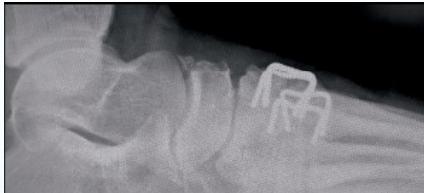

Orthopedic Staples

- Indications:

- Foot surgery

- Epiphysiodesis to correct lower limb deformity